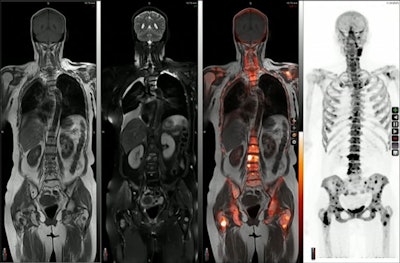

Both PET and MRI scanners are used in cancer imaging, with PET/MRI hybrid scanners developed about 12 years ago. These scanners can provide almost simultaneous detailed tumor assessments from multiparametric MRI with complementary physiologic information from PET. Thus, when images are fused -- essentially overlaid on one another -- by software during processing, the approach provides diagnostic value for clinicians not possible with either approach alone. Several studies support the role of PET/MRI for cancer evaluation, he noted.

An image presented during a molecular imaging session at the ISMRM meeting in Toronto showing the range of information a hybrid PET/MRI approach provides. Image courtesy of Hersh Chandarana, MD.There's no definitive answer to this question, but Chandarana noted a small study comparing the two in cancer patients imaged by both methods on the same day. Findings were noted for PET/CT but not for PET/MRI in just two out of 134 patients, while PET/MRI positively affected clinical management in 24 patients, he said.